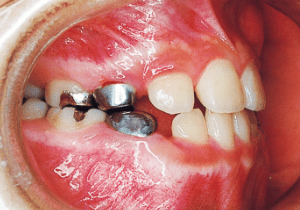

1 At start of treatment 7-21-’88

A case of diverted and cross bite during the deciduous dentition. Despite early treatment, the deviation progressively worsened with age, necessitating surgical treatment. At the initial visit, the patient had a deciduous dentition, and observation was planned (3). With the eruption of the permanent incisors, the mandible shifted slightly to the right, resulting in a cross bite (1) At this point, asymmetry can be confirmed in the front view. However, it is slight. The cephalometric X-ray reveals a structure with a slightly dominant mandible, but asymmetry in the mandibular ramus is not observed.